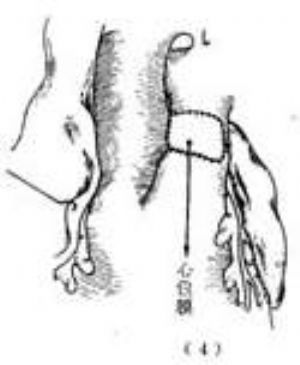

治療方法是在體外循環下施行手術,將右冠狀動脈開口連同其周圍的部分肺動脈壁從肺動脈切下後移位植入升主動脈根部前壁。由於右冠狀動脈較長,且起源於肺動脈前壁靠近升主動脈,移植術操作比較簡易(圖4)。